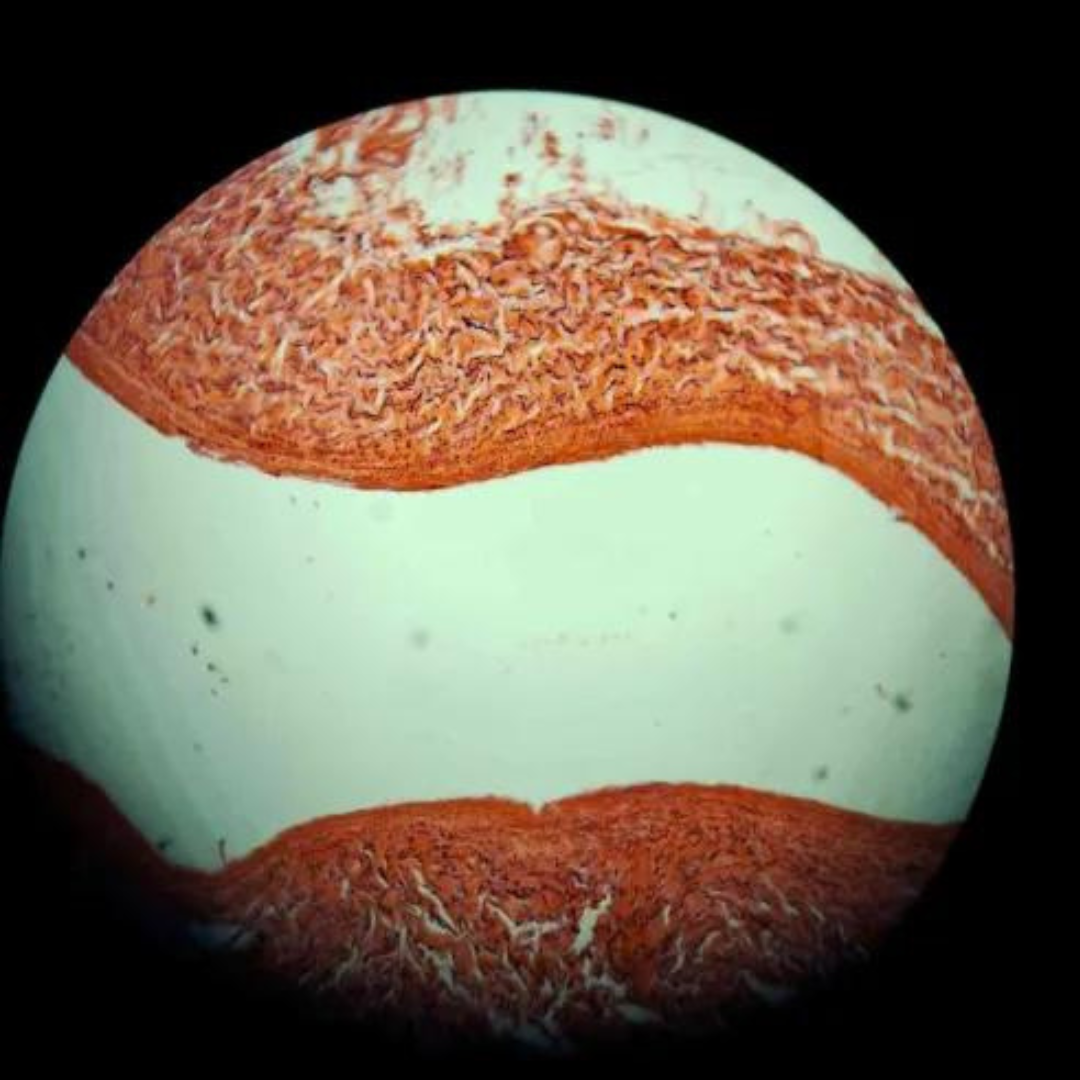

Elastic Arteries (Aorta)

Elastic Arteries (Aorta)

Elastic Arteries (Aorta)